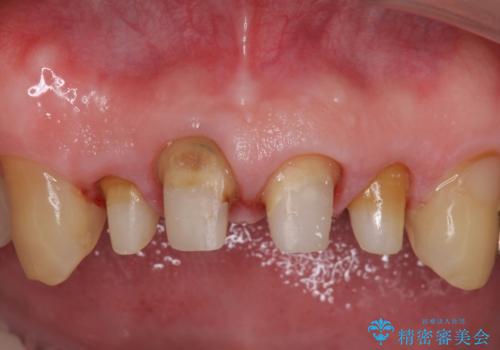

- 前歯の見た目が気になるといらっしゃった方の症例です。

再根管治療後、オールセラミッククラウンによる補綴を行いました。

右上2は歯茎のラインを整えるため歯周外科を行っております。